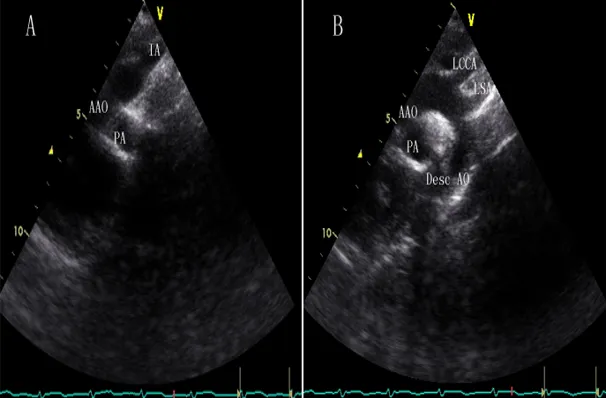

胸骨上凹主动脉弓长轴切面

探头位置:探头置于胸骨上窝;探头指向心脏,探测平过主动脉弓长轴。

观察内容:主动脉弓及分支、右肺动脉横断面。